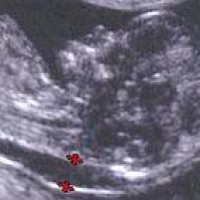

De echo

Bij de echo wordt bij de baby de dikte van de nekplooi gemeten. De nekplooi is een dun laagje vocht dat zich onder de huid in de nek bevindt. Alle ongeboren baby's hebben bij een zwangerschapsduur van 10 tot 14 weken een laagje vocht in het nekje, maar hoe dikker dit laagje vocht is, hoe groter de kans is dat de baby het Downsyndroom heeft.